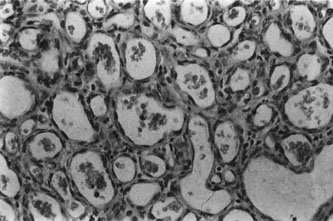

Histopathology

Histopathology reveals large, endothelium-lined, blood-filled spaces separated by fibrous septa and surrounded by a fine capsule (Figs. 7 and 8). Abundant, loosely distributed smooth muscle is present in the vascular walls, and scattered inflammatory cells may be seen.10,44 Histopathologic confirmation of the low-flow character of this lesion is seen by the presence of menisci in some vascular spaces and evidence of decomposed blood.

Fig. 8. Cavernous hemangioma. Histopathologic appearance of the widely dilated vascular spaces filled with red blood cells. Abundant, loosely distributed smooth muscle is present in the vascular walls, and scattered inflammatory cells can be seen (H&E, ´100).